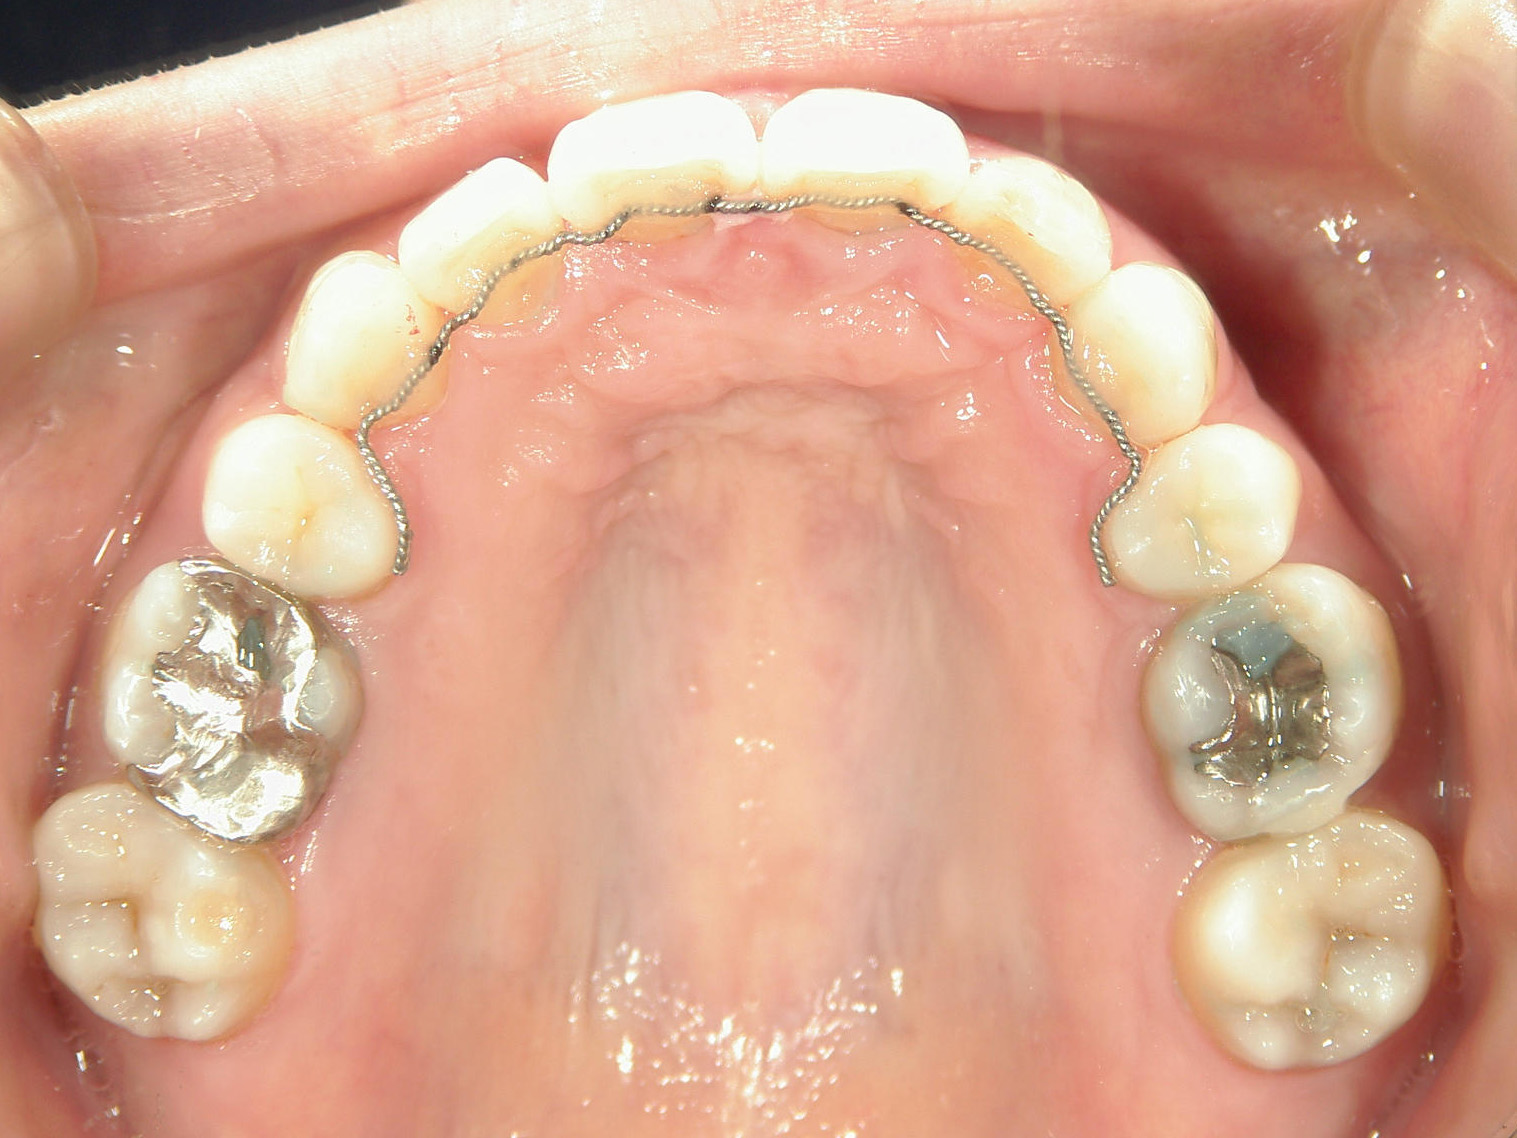

左右上 第一小臼歯(2本)、左右下 第二小臼歯(2本)を抜歯。

矯正装置(BH・QH)を併用。

ミニインプラント、アップライトスプリングを併用。

右下大臼歯(2本)をZ冠、E-MAX(On)に変更。